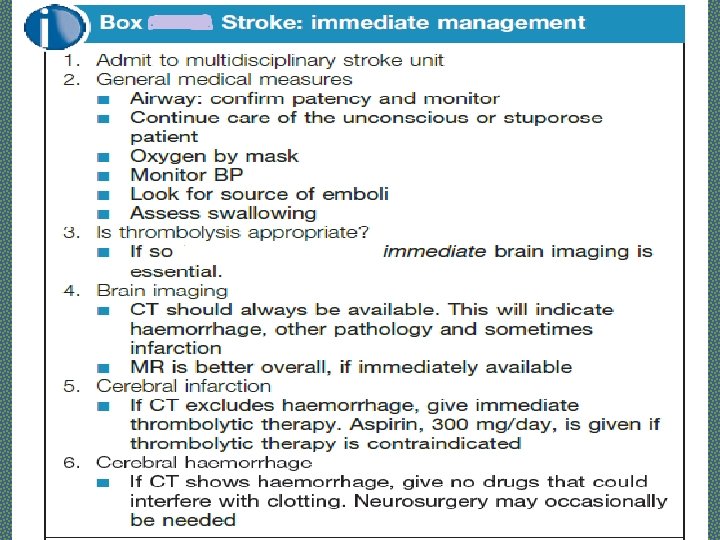

Investigations - STROKE The purpose of investigations in stroke is: • To confirm the clinical diagnosis and distinguish between hemorrhagic and thromboembolic infarction; • To look for underlying causes and to direct therapy; • To exclude other causes, e. g. tumour. • Sources of embolus should be sought

Investigations of Stroke Ø Brain Computed Tomography (CT) Scan Ø Magnetic resonance imaging (MRI) Ø Computed Tomography Arteriogram and Magnetic Resonance Arteriogram: Aneurysm, AV malformation Ø Carotid Ultrasound Ø ECG and Echocardiography Ø Lumber Puncture: Subarachnoid Hemorrhage

Investigations - STROKE Ø Routine bloods (for ESR, polycythaemia, infection, vasculitis, thrombophilia, syphilitic serology, clotting studies, autoantibodies) Ø Blood Sugar Level Ø Fasting Lipid profile Ø Chest X-ray Ø ECG and Echocardiography Ø Carotid Doppler studies Ø Lumber Puncture: Subarachnoid Hemorrhage

Investigations - STROKE • Imaging in Acute Stroke. • Non-contrast CT: will demonstrate haemorrhage immediately but cerebral infarction is often not detected or only subtle changes are seen initially.